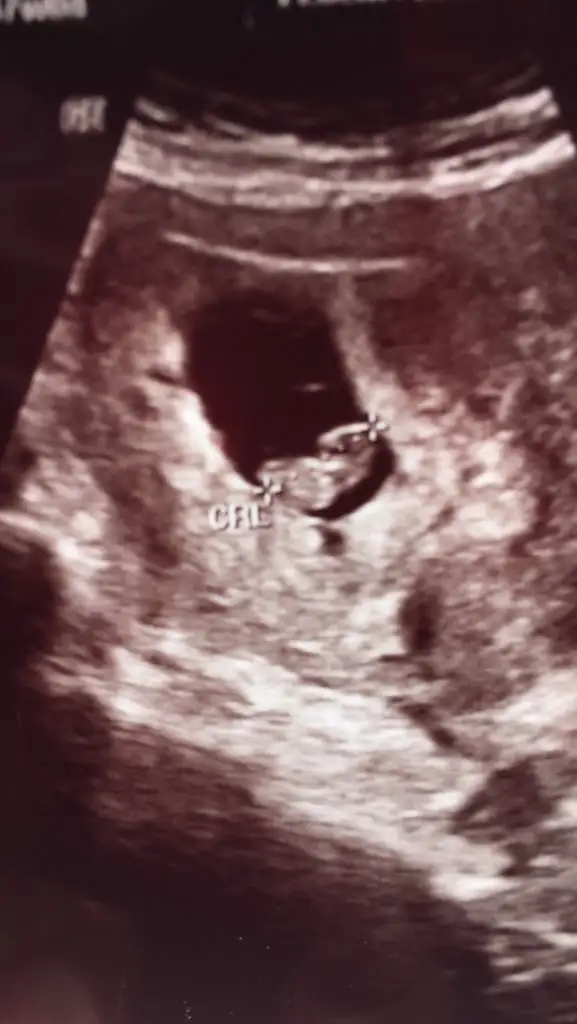

Kodlar benim bebiş 8haftalık burda tahmini olan var mi 😍🧿